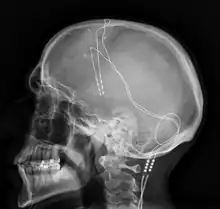

Lateral X-ray of the head: Deep brain stimulation in Obsessive–compulsive disorder (OCD). 42-year-old man, surgery in 2013.

DBS has been used in a small number of clinical trials to treat people with severe treatment-resistant depression (TRD).[44] A number of neuroanatomical targets have been used for DBS for TRD including the subgenual cingulate gyrus, posterior gyrus rectus,[45] nucleus accumbens,[46] ventral capsule/ventral striatum, inferior thalamic peduncle, and the lateral habenula.[44] A recently proposed target of DBS intervention in depression is the superolateral branch of the medial forebrain bundle; its stimulation lead to surprisingly rapid antidepressant effects.[47]